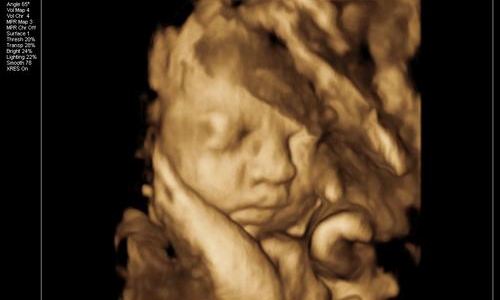

因为宝宝在子宫内发育的非常好,活蹦乱跳的。半个小时,朋友拿着四维彩照的照片一言难尽。

这也太丑了吧!朋友说自己和老公的长相都不差,为什么生育的孩子确实塌鼻梁、大鼻孔、厚嘴唇呢?

那山根宽的像座独木桥,整个一阿凡达!欲哭无泪的朋友觉得打击太大,连着好几天都沉浸在悲伤中不能自拔。

胎儿的面部脂肪还没有完全堆积,因此从四维看到的脸蛋来说是比较丑的,类似于外星人。头部和身体的占比例大概是2:1,以成年人的视觉来看可不是怪异么。

再者,孕妇拍摄四维的目的,便是排除胎儿面部是否畸形。所以会根据声波成像技术来填充图像,再将口、鼻、眼等细节放大。

但是小宝宝的口耳鼻实在太细节,声波反弹较弱,因此连接到电脑上后会另外填充成像。毕竟四维彩照和我们平时拍照的像素不一样,它是由彩超探头采集到的数据以此合成一个大致的影像。

那么打印出来后自然模糊,边缘不清晰,导致小宝宝的五官和肢体看起来扭曲变形。一定程度上*化丑**了宝宝,让新手爸妈们怀疑人生。

所以,在探头勘测超声波影像时,胎儿在动。加上胎儿整个是泡在羊水里面,左动一下,右动一下,拍摄出来的成像难免会失真。